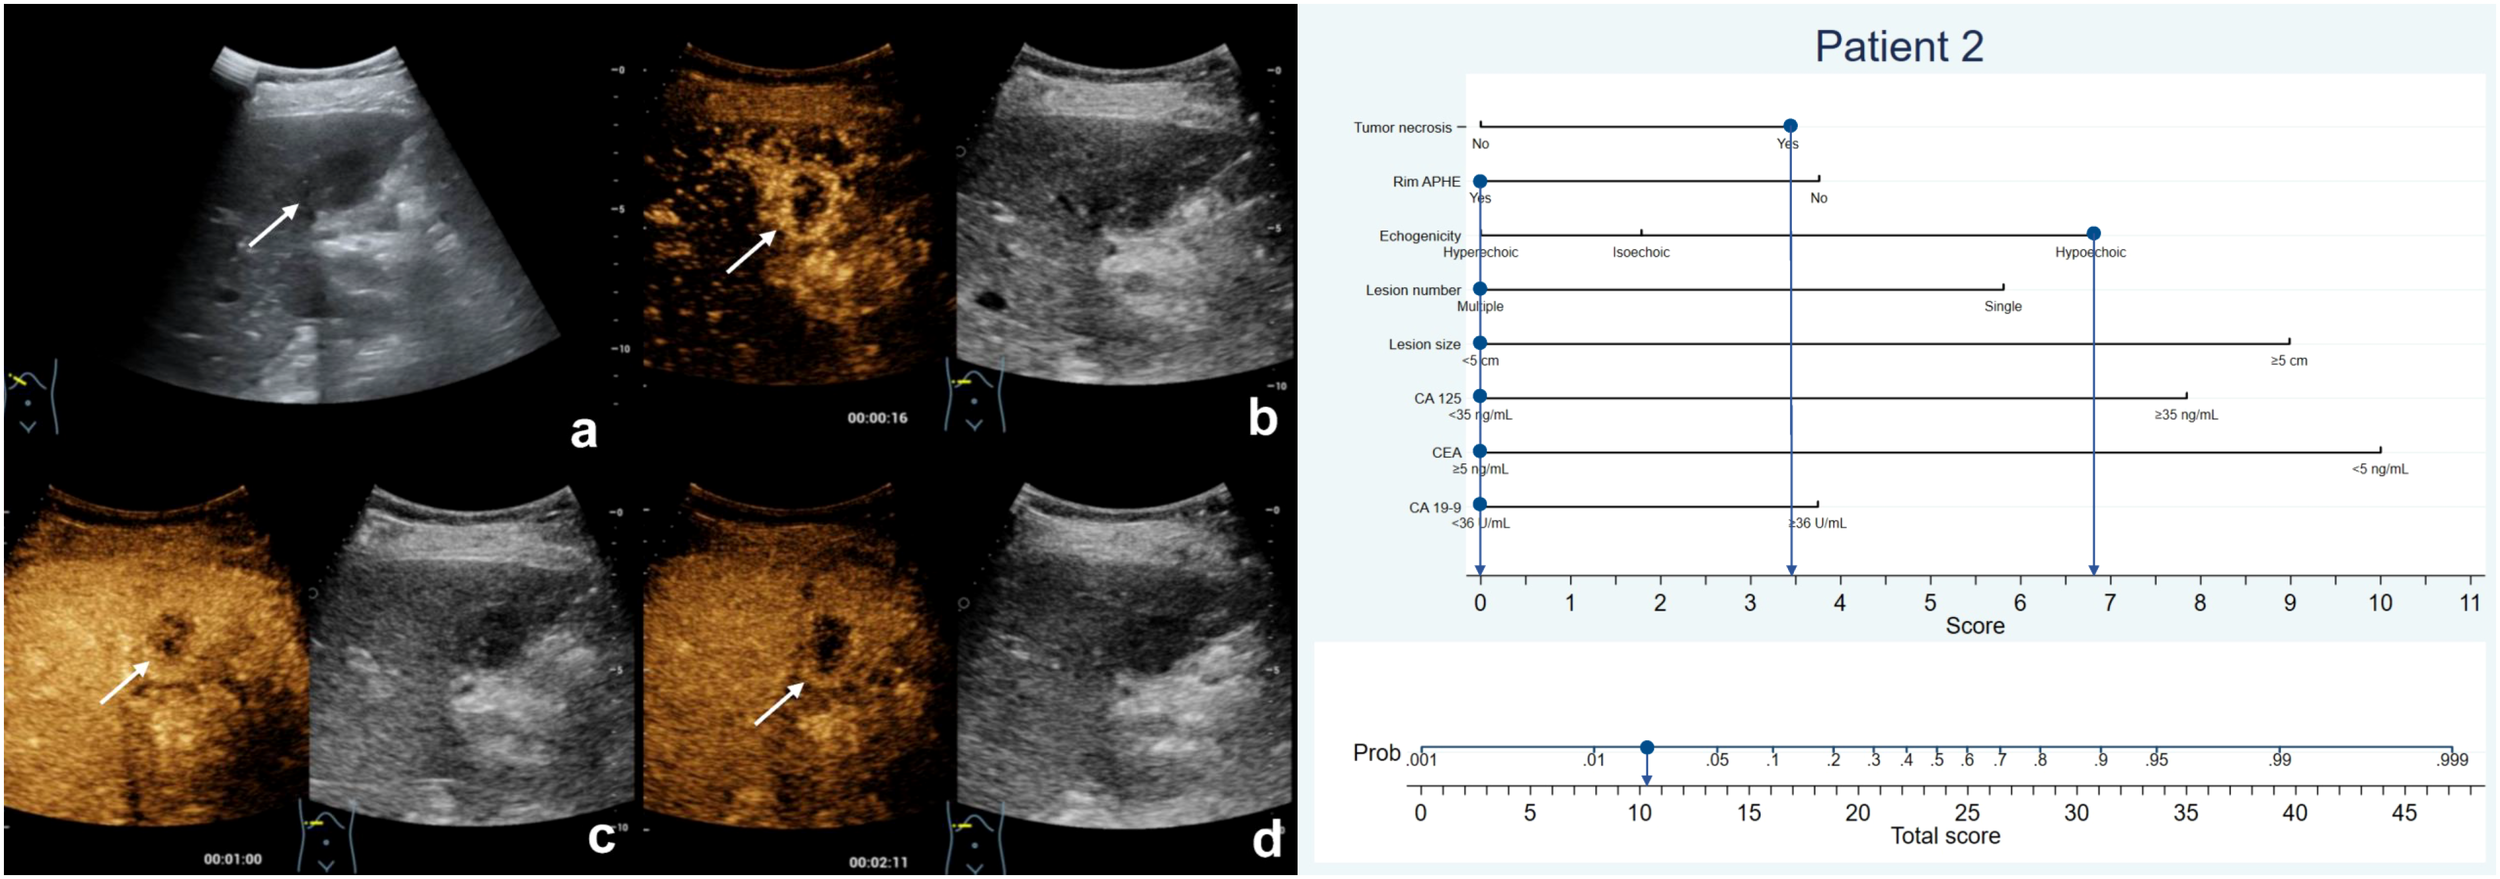

Figure 3 The patient was a 57-year-old man with a 6.1-cm isoechoic solid lesion in the liver (A). Hetero-hyperenhancement was observed during the arterial phase (B), and the lesion showed necrosis areas in the central on contrast-enhanced ultrasound (B–D). The serum level of CA125 and CA19-9 were elevated, while CEA level was normal. Based on the nomogram, a total of 45.2 points were assigned to the patient, corresponding to a probability of more than 90% of having MF-ICC. Postoperative pathological examination confirmed the diagnosis of MF-ICC.

Figure 4 The patient was a 75-year-old female who presented with several hypoechoic lesions in liver, with the largest one measuring 2.5-cm in diameter (A). Rim hyperenhancement of the tumor was observed during the arterial phase (B), and contrast-enhanced ultrasound revealed necrotic areas within the tumor (B–D). The patient exhibited elevated serum CEA levels but normal CA19-9 and CA125 levels. The nomogram score assigned to the patient was 10.2, indicating a less than 10% chance of developing MF-ICC. Pathological analysis confirmed liver metastatic adenocarcinoma originating from colon.